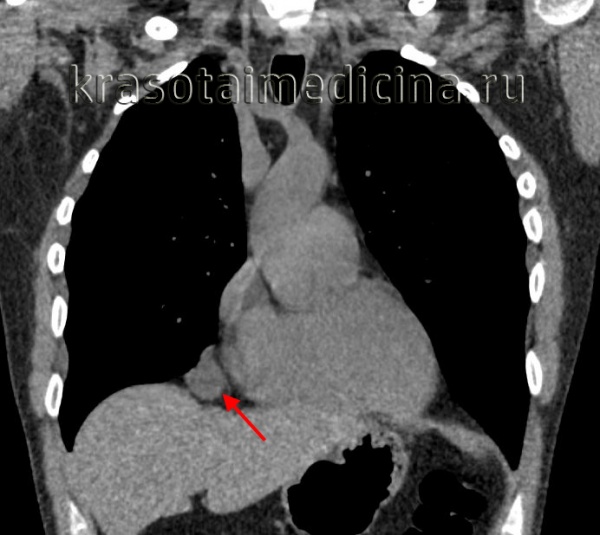

Полость бронхогенной кисты средостения изнутри выстлана эпителием цилиндрического или реснитчатого типа. Внутри кисты содержится прозрачная или мутноватая желатинообразная, вязкая масса, которая, при наличии связи кисты с бронхиальным деревом, может нагнаиваться. Бронхогенные кисты средостения обычно располагаются позади бифуркации трахеи и тесно соприкасаются с трахеей или главными бронхами, иногда - пищеводом. Обычно они имеют однокамерное строение и достигают размеров 7-10 см в диаметре.

Наибольшее значение для диагностики бронхогенных кист имеет рентгенологическое исследование (рентгеноскопия, рентгенография, пневмомедиастинотомография). Решающим критерием в установлении диагноза является определение локализации образования и его связи с окружающими органами. Бронхогенные кисты располагаются, как правило, в непосредственной близости к трахее (к ее боковым стенкам или бифуркации), т. е. в среднем или в заднем средостении.

Форма кист в значительной степени обусловливается их расположением: паратрахеальные бронхогенные кисты имеют вытянутую, часто грушевидную форму, а расположенные в области бифуркации — округлую или яйцевидную, при этом более узкая часть кисты направлена в сторону бифуркации. Вертикальный размер бронхогенной кисты всегда превышает горизонтальный (6, 13].

На обзорной рентгенограмме и томограмме они всегда единичные и имеют правильную округлую форму, в отличие от полициклических контуров увеличенных бифуркационных и корневых лимфоузлов, с которыми и приходится проводить дифференциальную диагностику. Компьютерная рентгеновская, магнитно-резонансная томография или УЗИ позволяют определить, что содержимым новообразования является жидкость, и на основании этого диагностировать кисту.